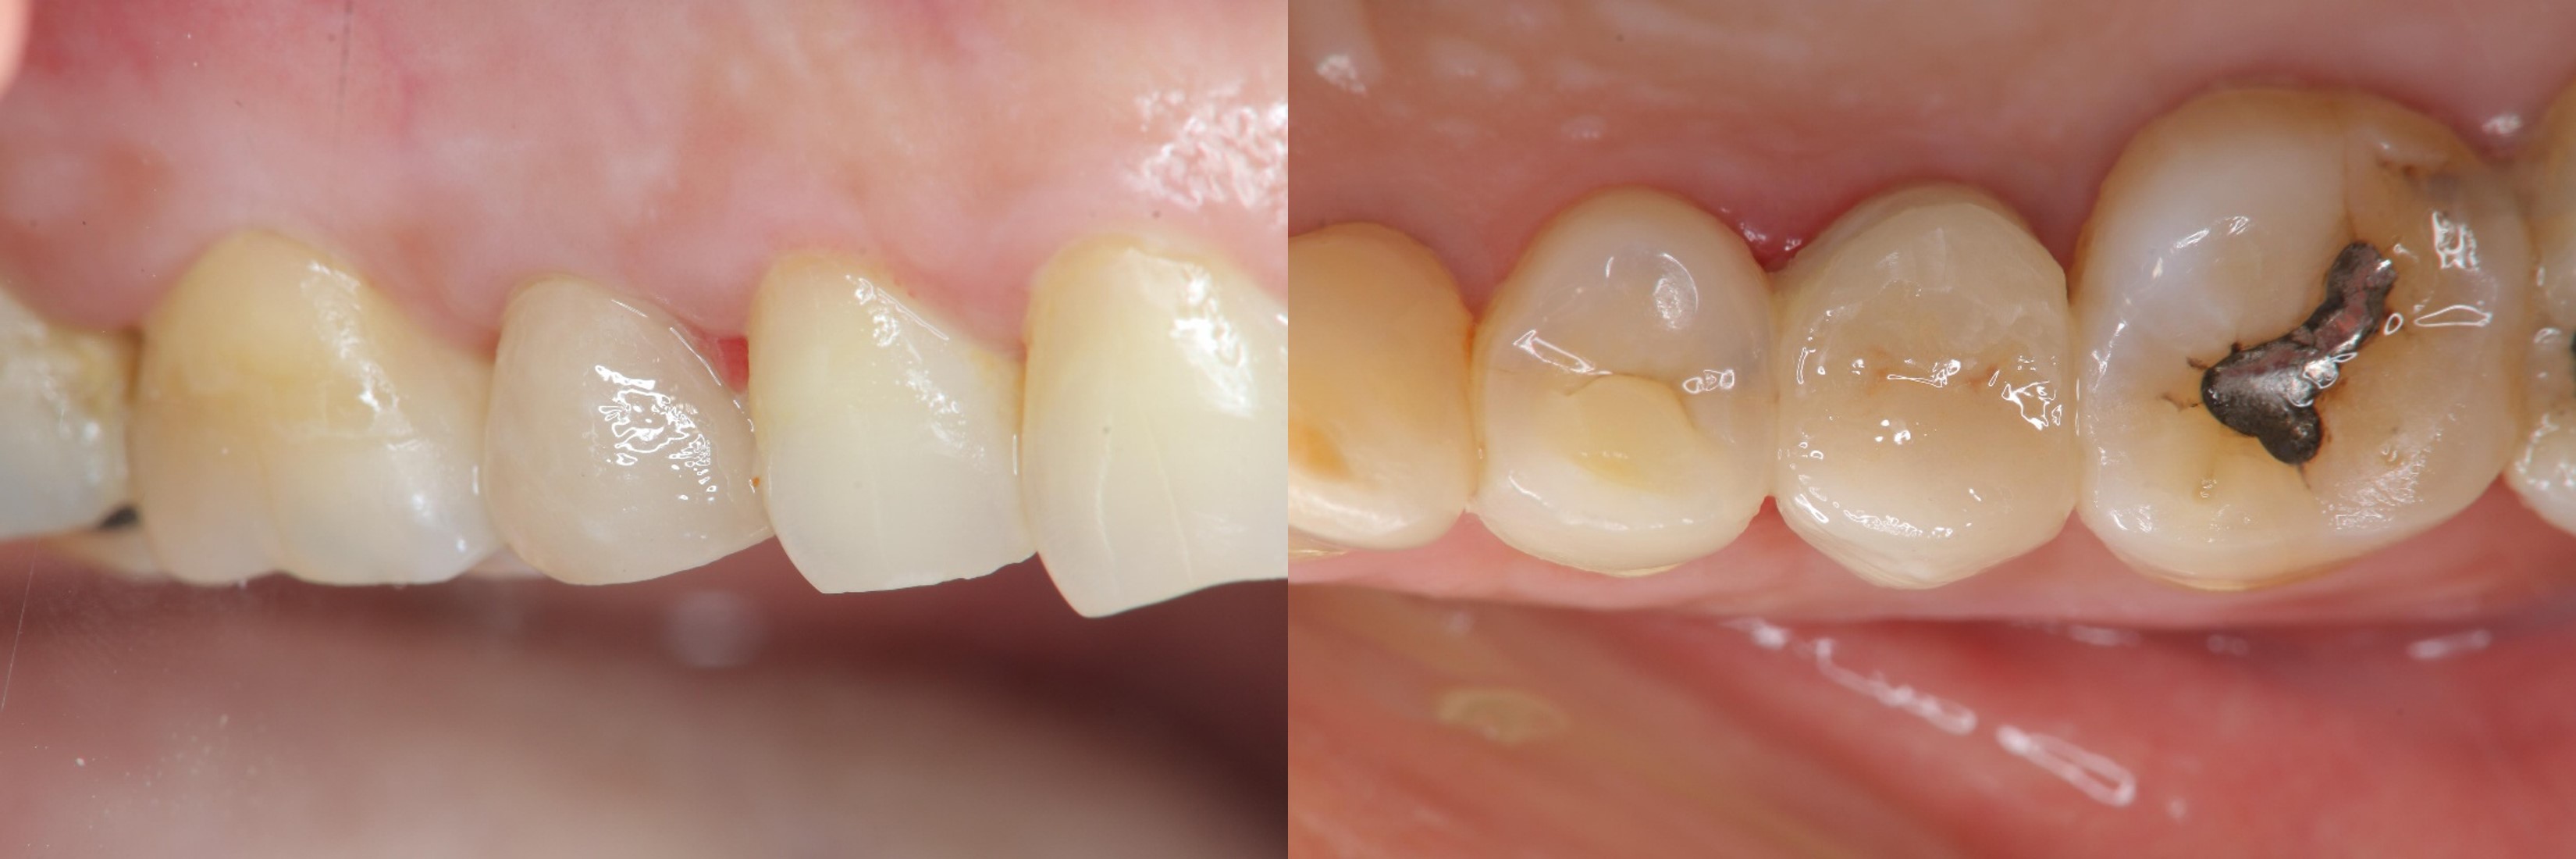

治療前,嚴重二次蛀牙

根管治療後再次牙裂

術前、術後比較